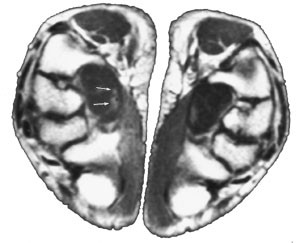

Inneklemming av medianusnerven som følge av stenose i kanalen er spesielt fremhevet som en viktig forutsetning for symptomutvikling (22, 23). Denne antakelsen bygger på en rekke tidligere studier der man ved hjelp av konvensjonell røntgenundersøkelse eller computertomografi (CT) har beregnet arealet av karpalkanalen på ulike steder i kanalens forløp (22 – 26). Undersøkelser med beregning av kanalens volum har ikke kunnet vise noen forskjell mellom pasienter med karpaltunnelsyndrom og kontrollpersoner (27). Det er vist at karpalkanalen er trangest i den distale del både hos symptomatiske og asymptomatiske personer (27) (fig 1). I tidligere studier er det påvist økt trykk i karpalkanalen hos pasienter med karpaltunnelsyndrom (28, 29). Det høyeste trykket ble målt i kanalens distale del, noe som støtter antakelsen om at medianusnerven er spesielt utsatt for mekanisk avklemming i dette området (29). For degenerative sykdommer i håndleddet, inflamatoriske sykdommer som f.eks. revmatoid artritt, graviditet med ødemdanning, akromegali og hypotyreose er sykdomsmekanismen antatt å være reduserte plassforhold i karpalkanalen (8). For andre tilstander, slik som diabetes mellitus, vaskulittforandringer og arvelig form for trykknevropati, regner man med at årsaken til karpaltunnelsyndrom er at medianusnerven har redusert evne til å tåle trykk fra omkringliggende vev (8, 30).

Degenerative forandringer i medianusnerven som følge av generell nevropati, vaskulittforandringer i nerven eller annen sykdomspåvirkning er kjent å kunne disponere for mononevropatier. I tillegg kan naturlige anatomiske variasjoner spille en rolle. For eksempel er det rapportert at forgreninger av nerven (bifid medianusnerve) kan være forbundet med karpaltunnelsyndrom (fig 2) (32). Andre anatomiske predisponerende faktorer er persisterende medianusarterie i karpaltunnelen og muskelanomalier i karpalkanalen (33, 34).